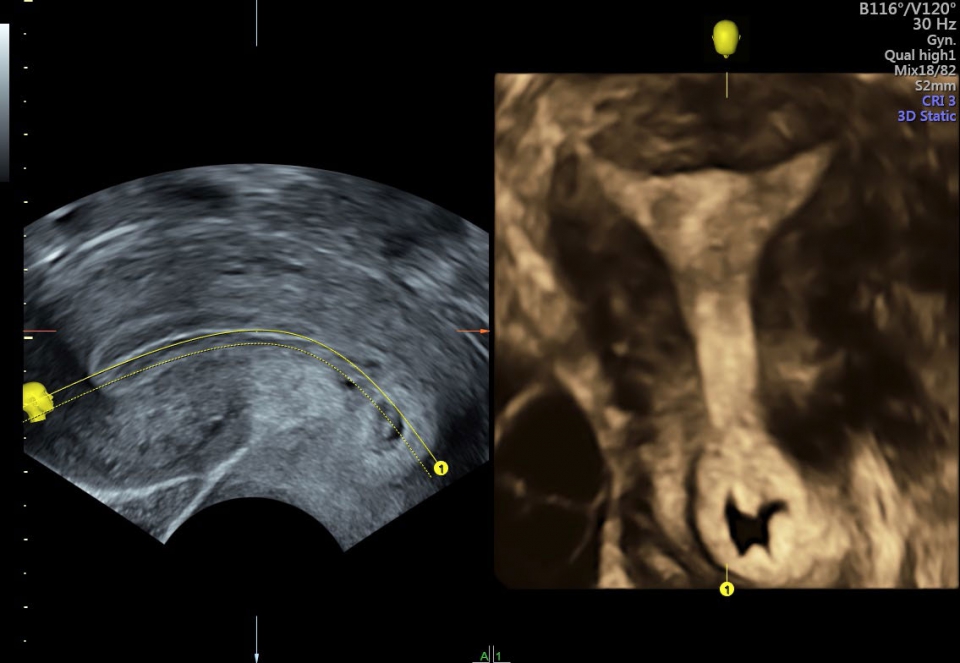

УЗИ аппарат Voluson S10 позволяет проводить обследования высочайшего уровня с максимальной точностью диагностики. Благодаря технологии Voluson Core Architecture достигнут высокий уровень качества изображений с возможностью последующей обработки и анализа даже после проведения скрининга. Технология HDlive делает изображения удивительно реалистичными и объемными.

• SonoRenderlive (Автоматическое объемное изображение): Эта функция упрощает получение объемного изображения путем автоматического выбора положения плоскости визуализации для 3D- и 4D-режимов. Это сокращает необходимость вручную настраивать параметры и упрощает процесс получения объемных изображений.

• SonoNT (Оценка воротникового пространства) и SonoIT (Оценка внутричерепного пространства): Эти технологии позволяют проводить полуавтоматическую оценку толщины воротникового пространства и размеров IV желудочка головного мозга плода в I триместре беременности. Они обеспечивают более точную оценку этих параметров с минимальными усилиями.